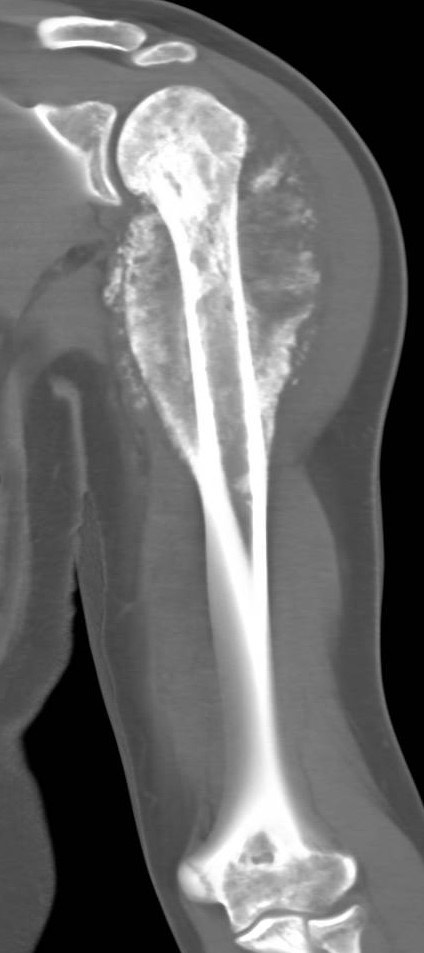

1891. Ребенку 14 лет с жалобами на боли в плече выполнена компьютерная томография, рентгенологическая картина соответствует